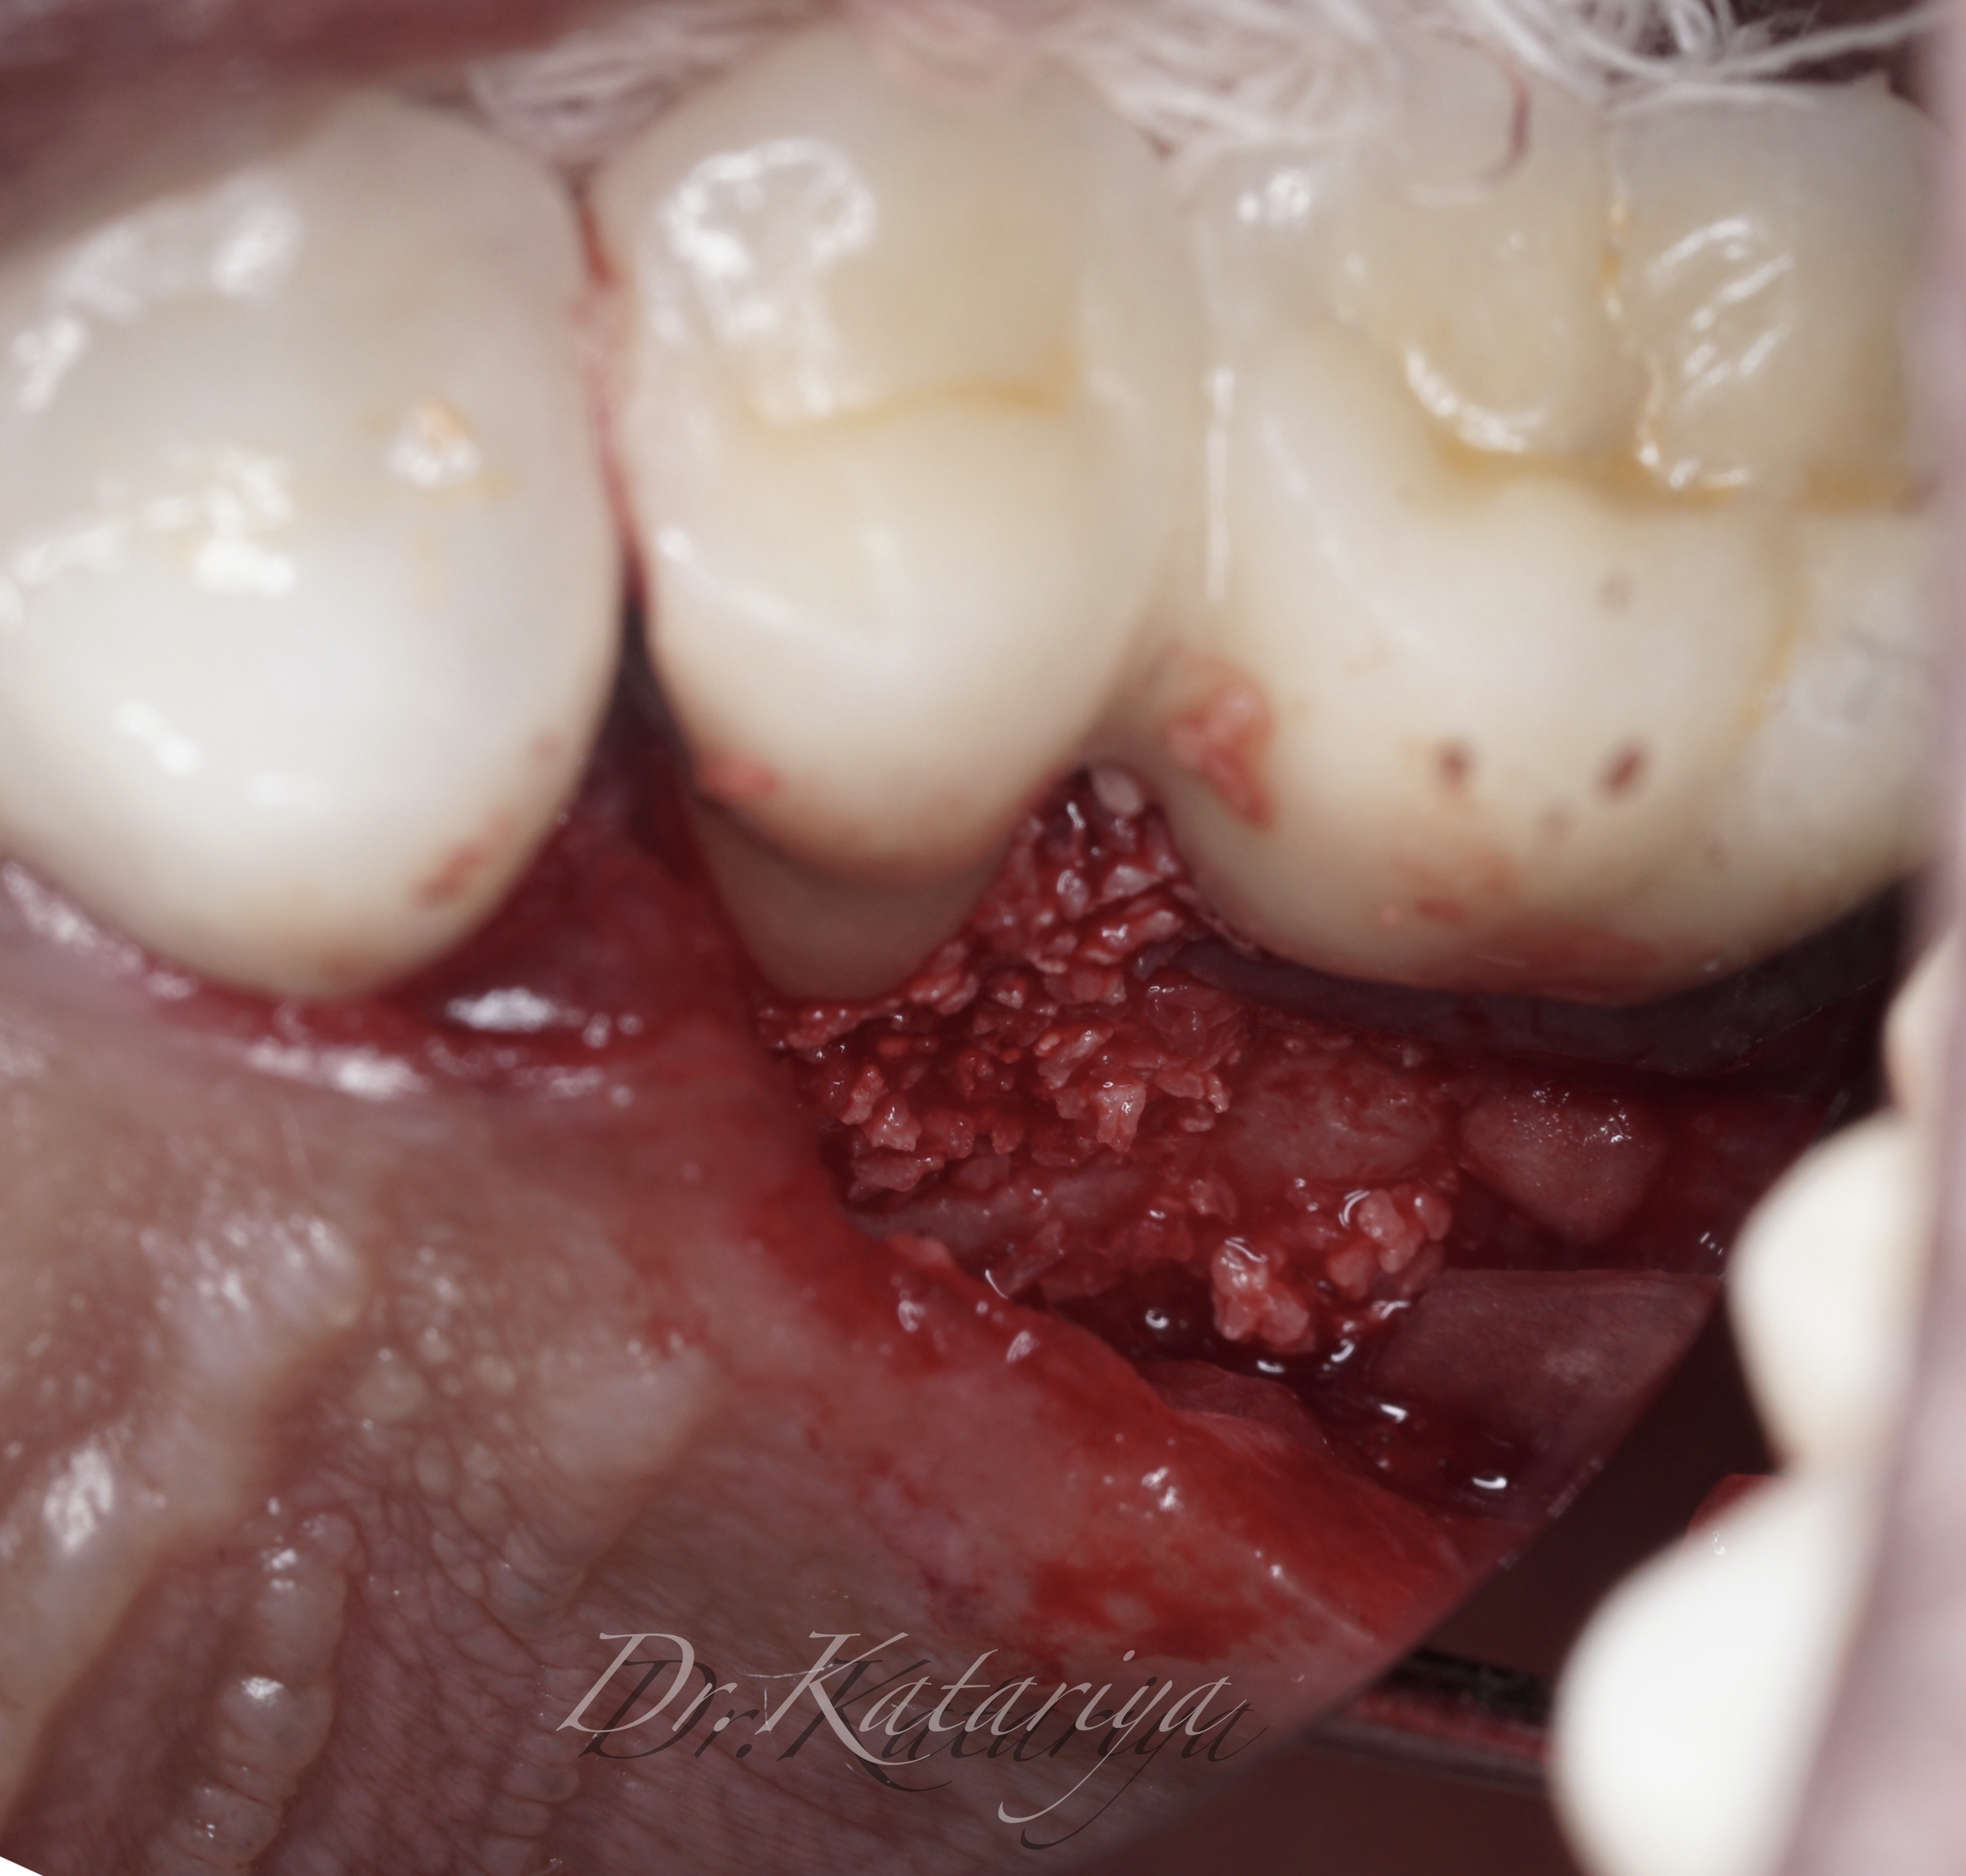

MINIMALLY INVASIVE PERIODONTAL MICROSURGERY

CARL ZEISS MICROSCOPE

with Bone defect captured in Real Time